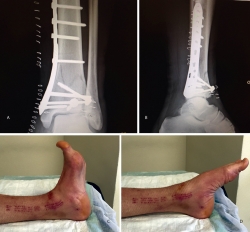

En cuanto al postoperatorio, inmovilizamos al paciente con una férula de yeso hasta las 3 semanas. A partir de ese momento, colocamos una férula de material termoplástico que se puede retirar para movilizar el tobillo, iniciando la carga con una bota ortésica de tipo Walker a las 6-8 semanas (Figuras 6 a 11).

Figura 17. Caso 3: fractura tipo C. Radiografías sin tracción y con tracción comprobando la reducción.

Figura 18. La tomografía computarizada muestra los fragmentos principales de la fractura, estando desplazado el Tillaux que se reduce con la tracción.

Figura 19. Colocación del tornillo en el Tillaux con la extremidad en tracción y posteriormente la placa MIPO (minimally invasive plate osteosynthesis).

Figura 20. Radiografías postoperatorias y resultado final con movilidad completa en flexoextensión del tobillo.